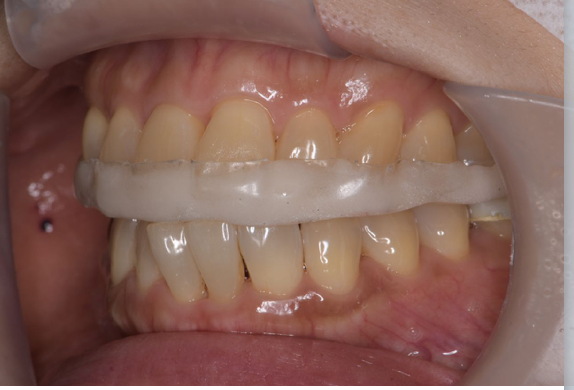

咬合

噛み合わせは見た目だけでは分からず、正確な診断には精密検査が必要です。

詳しく見る